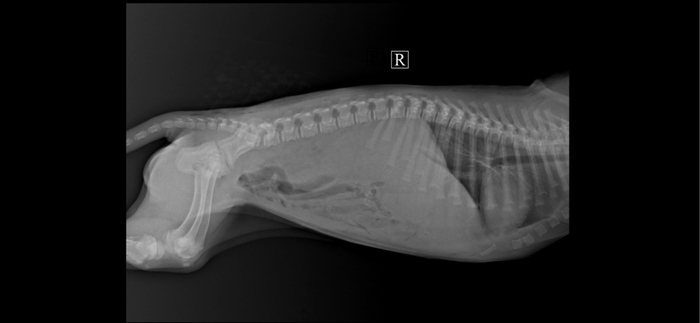

Сегодня Ржевский был на кастрации, сделал УЗИ и сдал анализы.

По УЗИ - острый холецистит и холангит. В мочевом пузыре большое скопление газа и взвеси.

По анализу мочи - присутствует кровь и запредельное количество белка.

Для установки диагноза, мочу отправили на бакпосев.

Так же сдали кровь на Лейкоз и Иммунодефицит. И Лейкоз РНК пришёл положительный.

Назначено: Урсофальк 1/4 капсулы 250 мг, 1 р/д на ночь. Курс 1 месяц.

Кладакса 250 мг 1/2т, 2 р/д или Амоксигард 0,5 мл п/к, 1 р/д. До готовности результатов бакпосева.

Масса 4,8 кг.